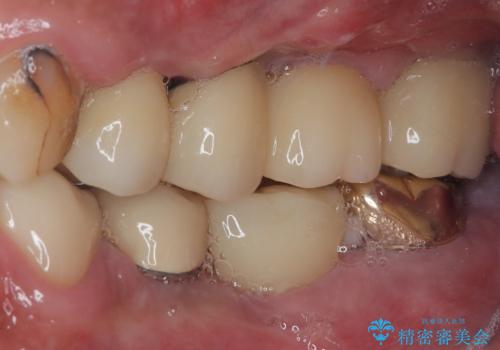

- 土台の歯が割れてしまって、歯がグラグラしているとのことで来院された患者様です。

いずれの歯も抜歯が必要な状態であり、抜歯即時埋入によるインプラント治療を行うこととしました。

右上奥歯は骨欠損の範囲が広いため、抜歯即時埋入は可能であっても、即日で仮歯を装着する即時荷重は難しいと判断されたため、手前の歯まで仮歯を装着することとしました。

強い咬合力により歯根破折を繰り返しているため、即日荷重あるいは早期荷重による他の歯への負担を軽減することが重要となります。

抜歯即時埋入インプラントは、咬合力によるトラブルを回避する、非常に有用な手段となります。